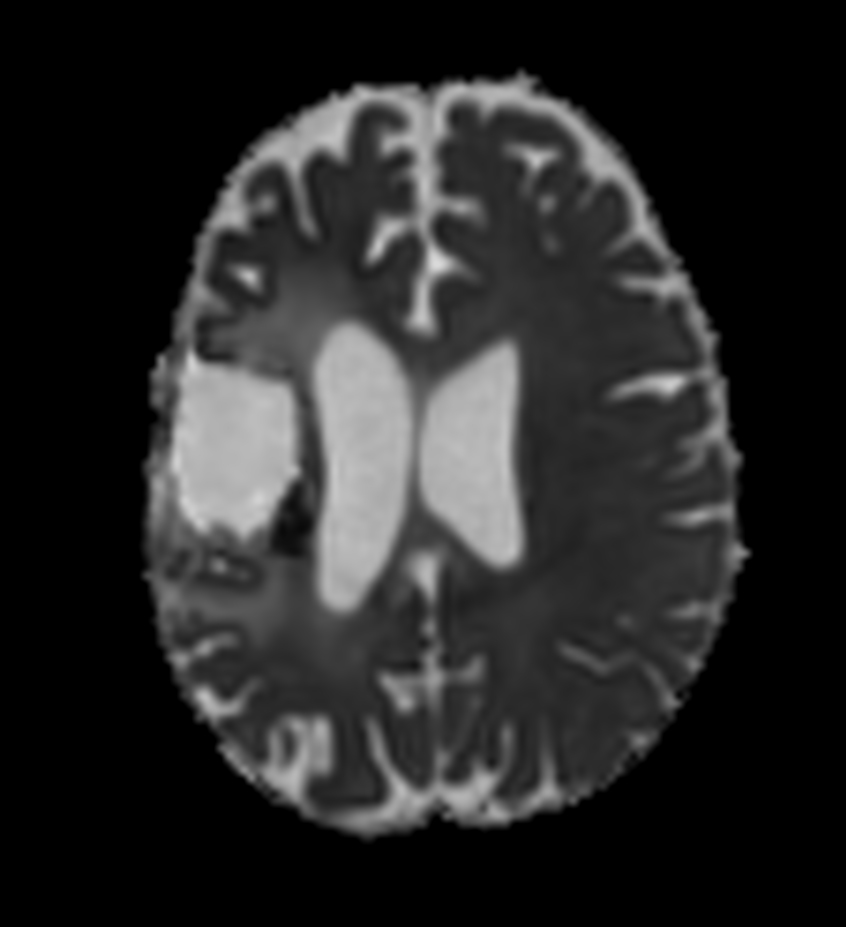

Axial DTI (b1000)

Axial DTI (ADC)

Axial DTI (eADC)